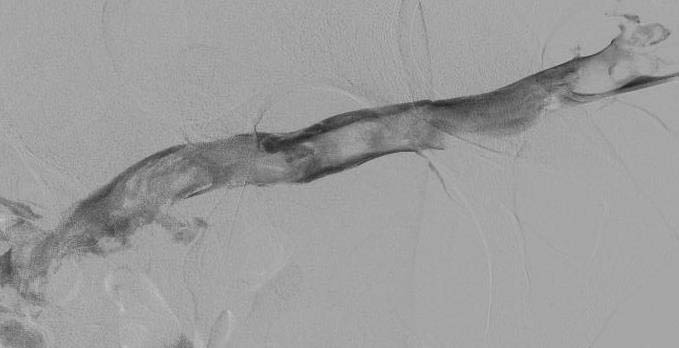

Промежуточный результат катетер-управляемого тромболизиса – появление минимального кровотока в исходно тотально тромбированных подвздошных и общей бедренной венах.

Финальный результат катетер-управляемого тромболизиса – полное восстановление кровотока с растворением всех тромбов в исходно тотально тромбированных подвздошных и общей бедренной венах.